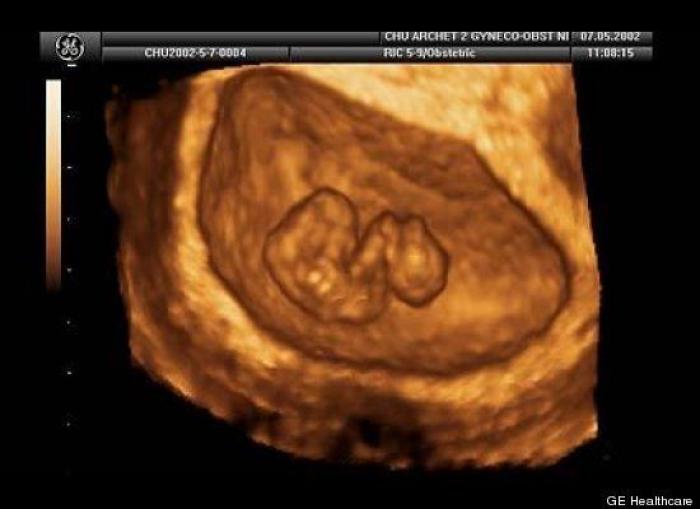

En esta galería puedes ver en fotos como es el desarrollo de un feto de semana en semana:

Desarrollo del feto, en fotos